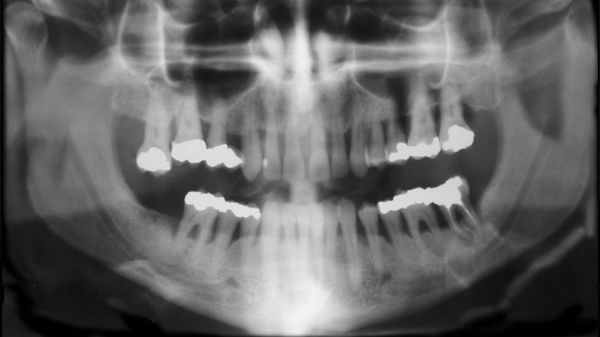

• ​Kan tandlossning och ledgångsreumatism hänga ihop?

Finns det en koppling mellan parodontit och reumatoid artrit? Det vill säga mellan tandlossning och ledgångsreumatism. Det vill en grupp forskare ta reda på och får nu drygt 700 000 kr till sitt förfogande av Eklund Foundation.